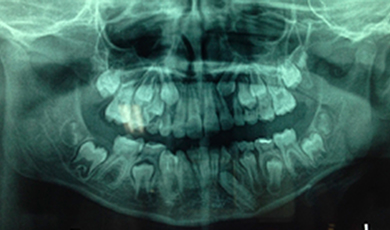

Canino inferior esquerdo incluso (dente 33)

As imagens abaixo retratam um caso clínico em que a paciente compareceu ao consultório para avaliação ortodôntica e por meio da imagem radiográfica (panorâmica) foi possível identificar que o canino inferior esquerdo (dente 33) encontrava-se incluso, sendo necessária a intervenção ortodôntica para o seu tracionamento.